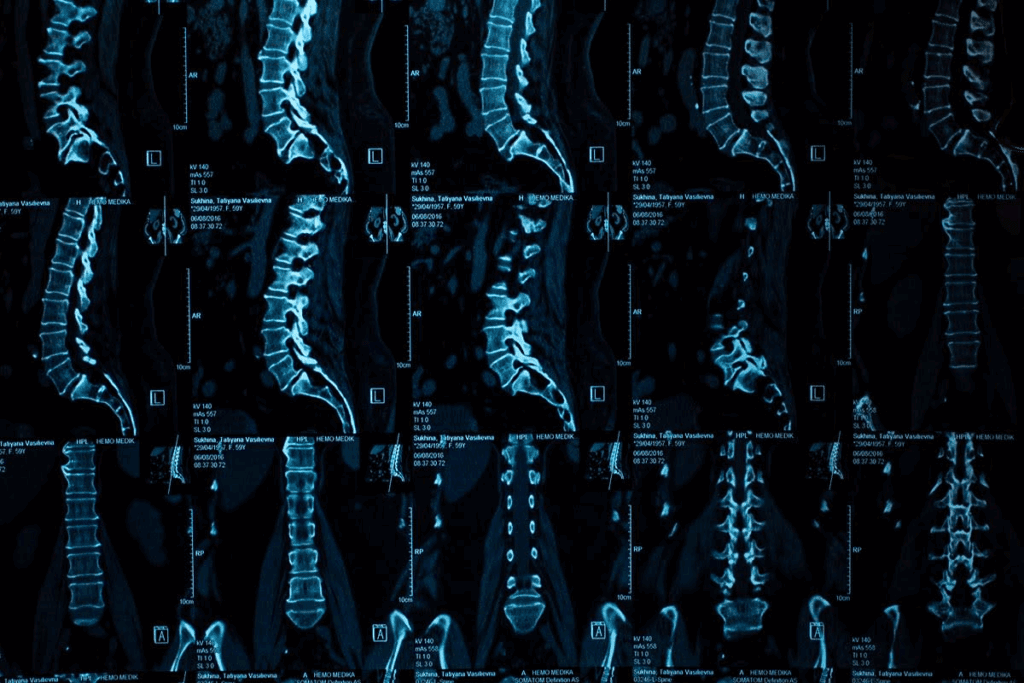

Degenerative disc disease is when the spinal discs wear out. The spinal discs are important for absorbing shock and keeping the spine flexible. With age, these discs can lose their effectiveness, leading to degeneration.

The discs dry out with age, becoming less flexible and more likely to crack or tear. This can cause pain and discomfort. If the degeneration is severe, it can irritate the nerves around it.

Spinal discs are like shock absorbers between vertebrae, helping with smooth movement and shock absorption. They have a tough outer layer and a soft inner part. As we get older, we lose water and become less flexible, which can cause pain.

A degenerated disc, on the other hand, has less water and is less flexible. It’s more likely to hurt and cause pain. The discs shrinking can make the vertebrae rub together, leading to inflammation and pain. Many things can speed up this degeneration, like genetics, lifestyle, and past injuries.